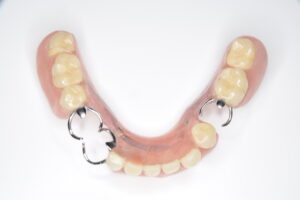

まず、保険のクラスプ義歯がどのような構造かをおさらいします。一般的なクラスプ義歯は、残っている歯に「クラスプ」と呼ばれる金属のバネを引っ掛けて入れ歯を支えます。

抜けた歯を補うために、歯ぐきと同色のプラスチックに人工の歯をつけ、その横に金属のクラスプが付く、という形です。

問題は、クラスプが歯にただ引っ掛けられているだけのため、硬いものを噛むと多少のがたつきが起こり、横からのねじれに弱い点です。

その結果、食べ物が挟まりやすく、噛むたびに支えている歯が揺さぶられます。入れ歯を外すときにも歯がさまざまな方向に揺れるため、歯に負担がかかるのです。